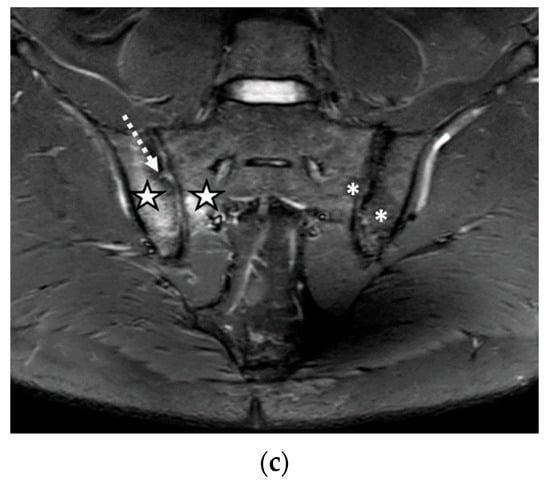

Figure 3.

The MRI aspect of the sacroiliac joints included pseudo-widening of both sacroiliac joints, with marked bone marrow edema (star) of both the sacrum and the right iliac bone, in the proximity of the ipsilateral sacroiliac joint space, right iliac bone erosions (discontinuous arrow), bilateral subchondral sclerosis (continuous arrow), and fat metaplasia (asterisk), affecting the left iliac bone, and the left part of the sacrum and backfill (arrowhead) of the left sacroiliac joint space: (a) T1-weighted sequence; (b) T2-weighted sequence (without fat suppression); (c) STIR sequence.